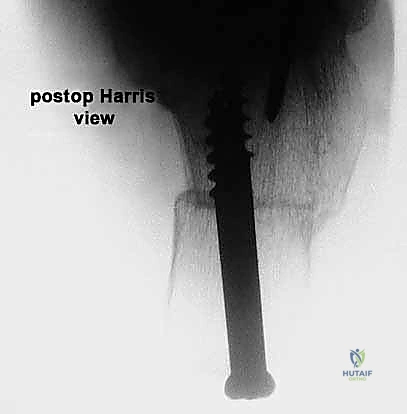

* Radiographs: We obtain true anteroposterior (AP) views of the shoulder in the plane of the scapula and axillary views. These allow us to evaluate glenohumeral arthritis, superior migration of the humeral head, and identify any abnormal bony anatomy.

FIG 3 • A. True AP radiographic view showing minimal superior migration and preserved joint space.

FIG 3 • A. Continued: True AP radiographic view.

FIG 3 • B. Axillary lateral view demonstrating joint space preservation and absence of osteophytes.

FIG 3 • C. Radiographic findings of degenerative arthritis with osteophyte formation and superior migration.

FIG 3 • D. Axillary lateral view showing osteoarthritis with early posterior glenoid wear, suggestive of a poor candidate.